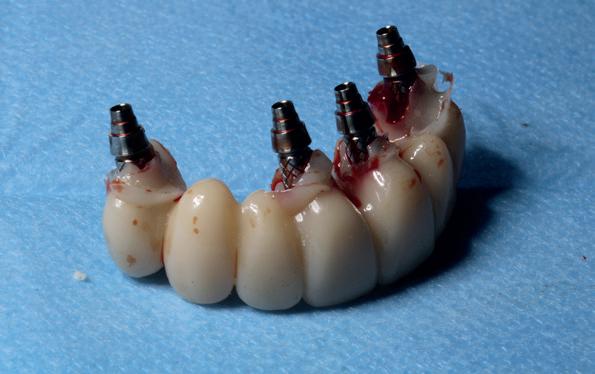

In de prothetische fase (zie foto’s) is in de bovenkaak gebruikgemaakt van verschroefde zirconia bruggen, die enkel buccaal zijn opgebakken. Deze bruggen zijn verlijmd op individuele, geanguleerde titanium abutments. In de onderkaak is een verschroefde kunststofbrug op een titaniumbasis (wrap-around) gemaakt. Voor deze combinatie is gekozen vanwege een minder hinderlijk tikkend geluid bij functie en kleinere kans op breuk van de keramiek. Een nadeel is verhoogde slijtage van de kunststof elementen, maar deze zijn in de jaren later eenvoudig te vervangen op de bestaande brug. Ondanks alle digitale mogelijkheden is de afdruk en registratiefase analoog uitgevoerd, omdat in ervaring van de behandelaren dit bij deze totale rehabilitaties op implantaten nog altijd de grootste precisie oplevert. Er is afgedrukt met impregum in individuele lepels en de pasvorm is gecontroleerd met rigide duralay bars. De relatie wordt vastgelegd zoals bij een volledige prothese met waswallen en pijlpuntregistratie. De opstelling in was wordt gepast en laatste correcties worden gemaakt in samenspraak met de patiënt, de restauratieve tandarts en de tandtechnicus. Na het vastzetten van de suprastructuren worden de schroefgaten afgesloten met composiet.

10. In de bovenkaak is gekozen voor 3 zirconium bruggen; in de onderkaak is gekozen voor een wrap-around met titanium

core.

11. In de bovenkaak is keramiek gebruikt en in de onderkaak kunststof (behandeling is